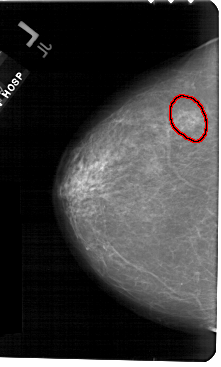

A_1562_1.RIGHT_CC

RIGHT_CC LINES 5266 PIXELS_PER_LINE 3226 BITS_PER_PIXEL 12 RESOLUTION 43.5 NON_OVERLAY

FILE: A_1562_1.LEFT_MLO.OVERLAY

TOTAL_ABNORMALITIES 1

ABNORMALITY 1

LESION_TYPE CALCIFICATION TYPE AMORPHOUS DISTRIBUTION CLUSTERED

ASSESSMENT 4

SUBTLETY 3

PATHOLOGY BENIGN

TOTAL_OUTLINES 1